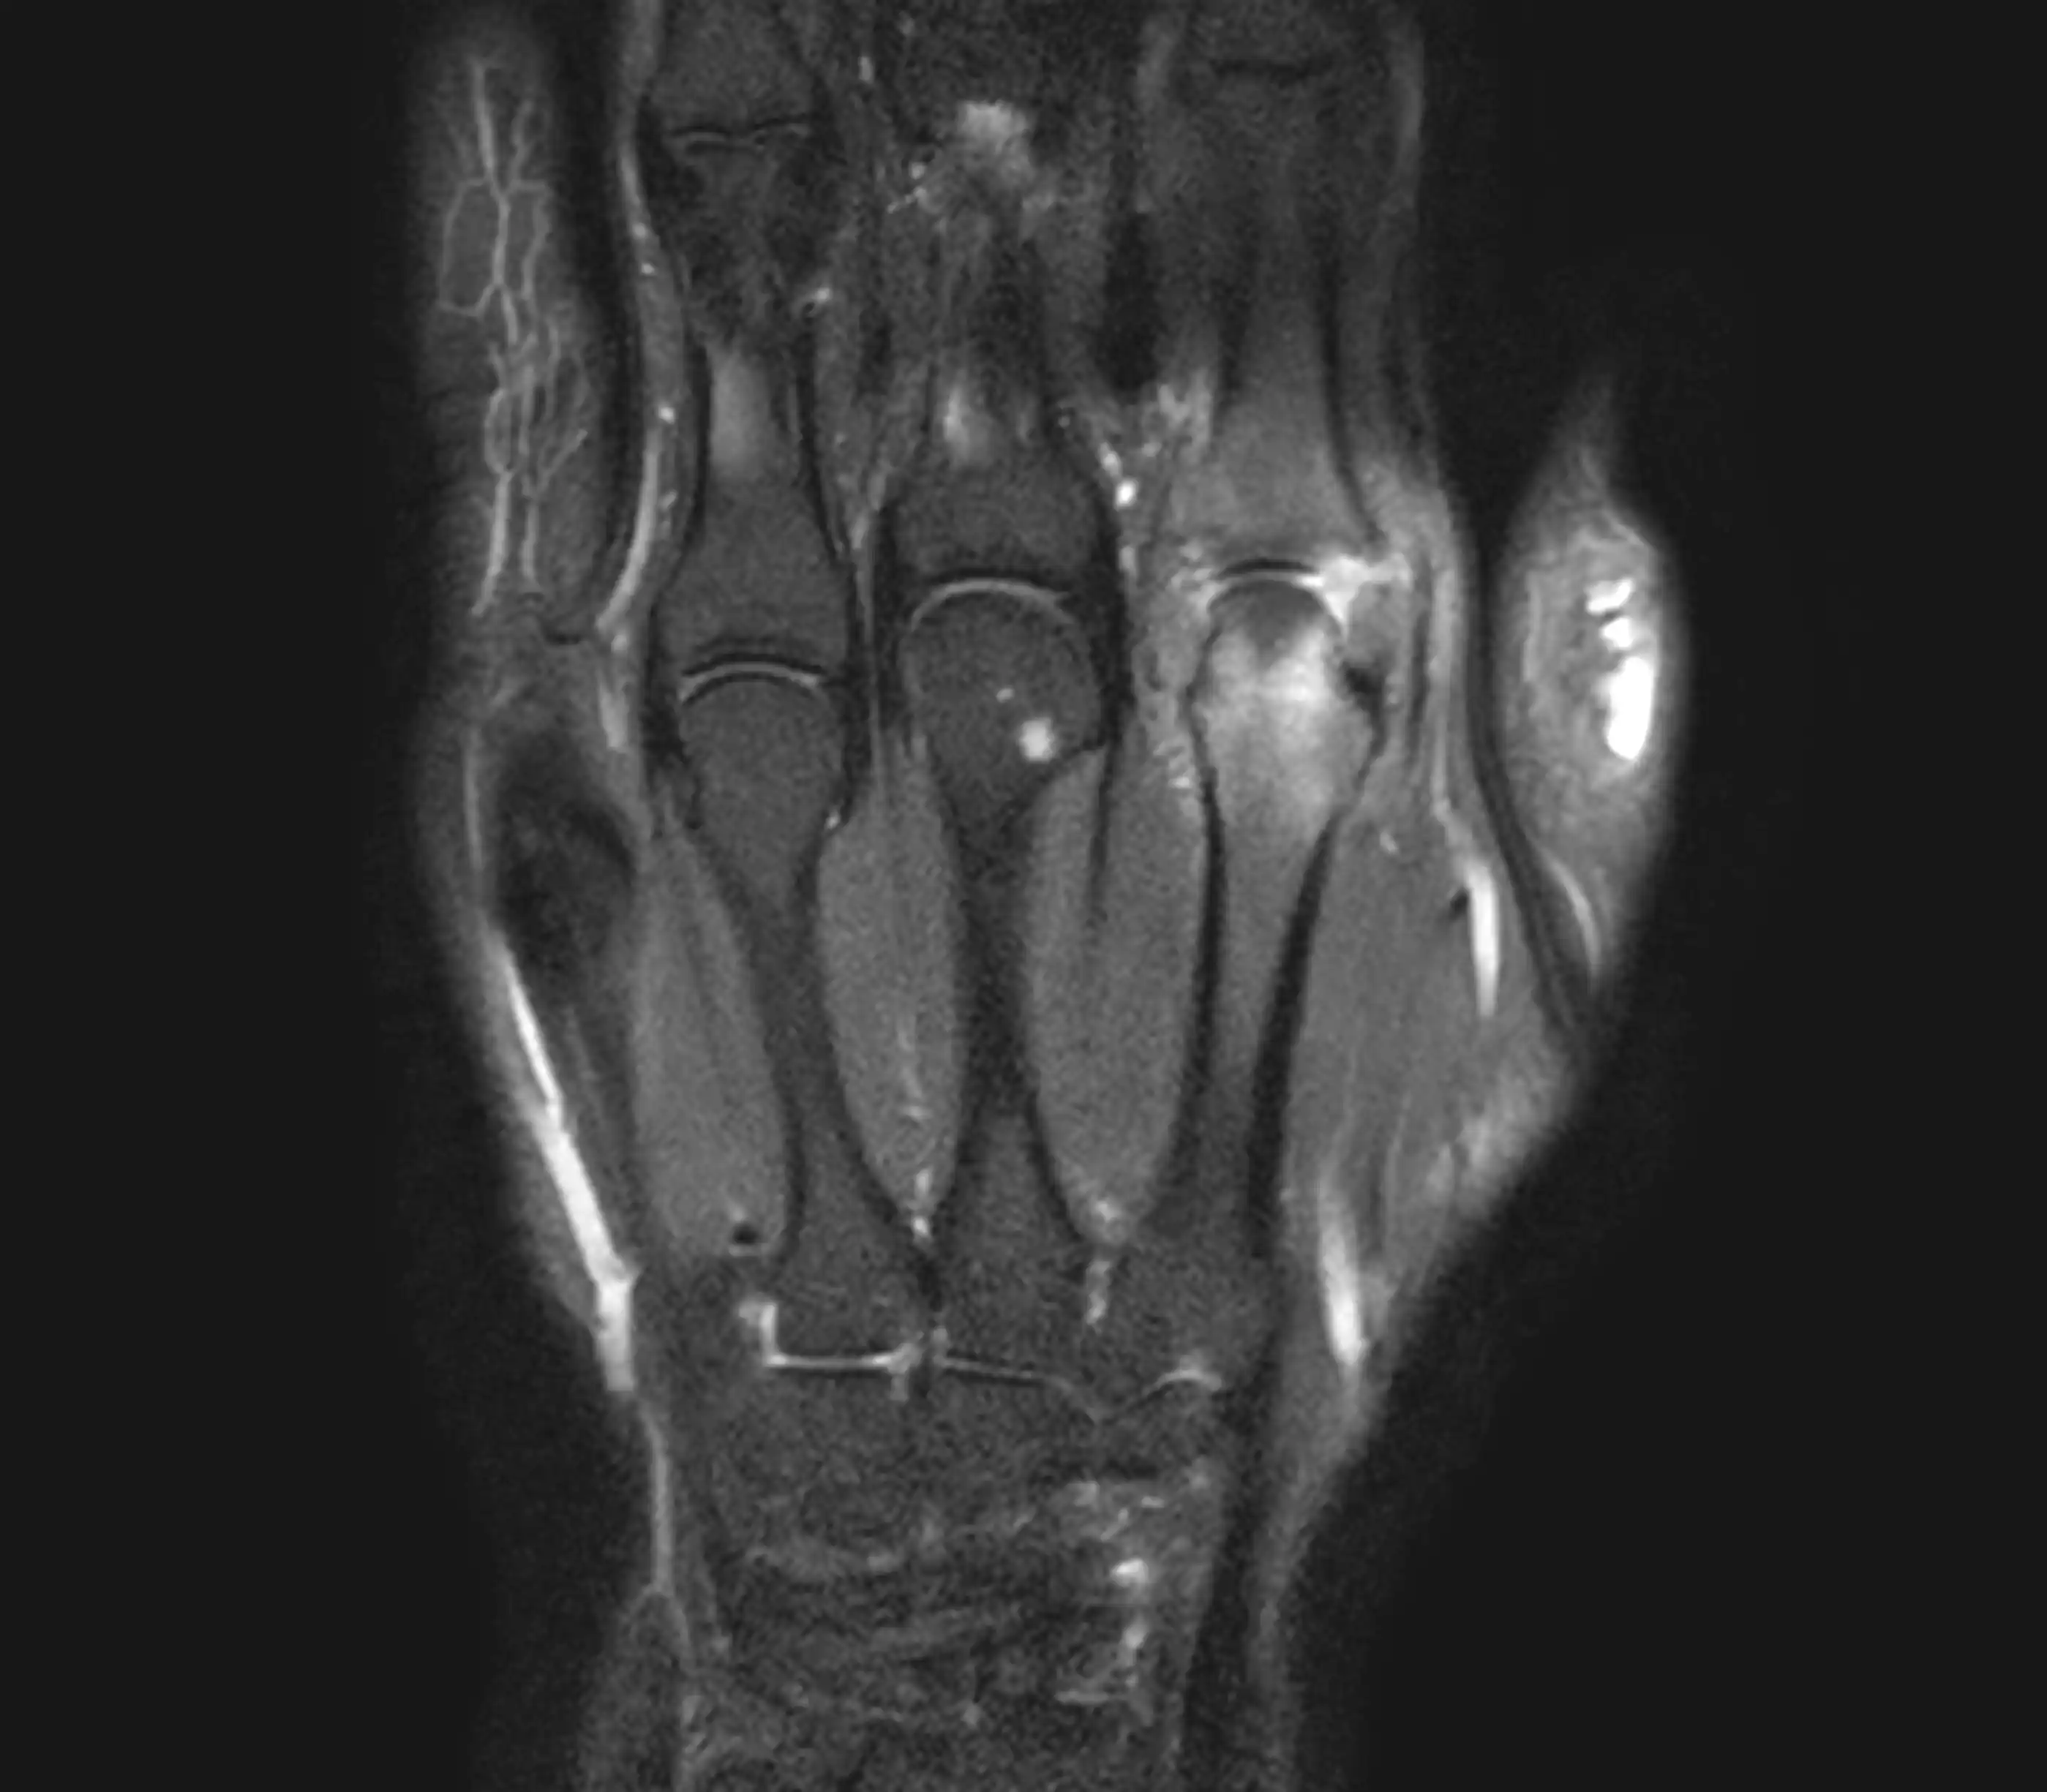

МРТ променезап’ясткового суглобу — це сучасний метод обстеження, який дозволяє детально оцінити стан кісток, зв’язок, сухожиль, хрящів, нервів та м’яких тканин у ділянці зап’ястя.

Магнітно-резонансна томографія допомагає виявити причини болю, обмеження рухливості та інші патологічні зміни у променезап’ястковому суглобі без використання рентгенівського випромінювання.

Що показує МРТ променезап’ясткового суглобу

МРТ дозволяє виявити:

- пошкодження зв’язок

- розриви сухожиль

- запальні процеси

- дегенеративні зміни суглоба

- травматичні ушкодження

- патології хряща

- новоутворення

- ураження нервів